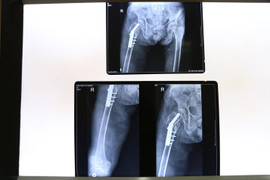

Cụ N.T.C. (101 tuổi) bị gãy liên mấu chuyển xương đùi phải do té ngã được các bác sĩ Bệnh viện đa khoa Đức Giang phẫu thuật thành công trong 40 phút.